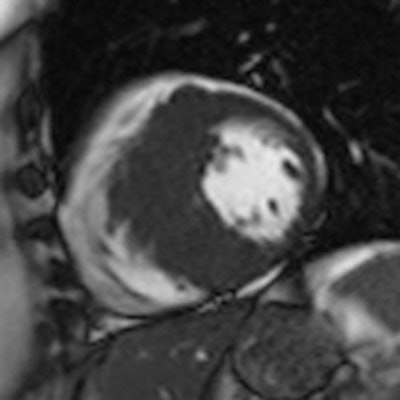

Cine MRI in short axis orientation in a patient with hypertrophic cardiomyopathy.

In workup, radiologists need to assess functional parameters to discover the extent of deterioration and its underlying pathological conditions, as well as assess myocardial status of the left ventricle in terms of whether the changes can be reversed or not. There are plenty of tools in the doctors' toolbox, including flow measurements, cine MRI, stress and rest perfusion, MR angiography, and high-resolution T1- and T2-weighted morphological imaging of both ventricles. In addition, images acquired 10 to 30 minutes after gadolinium administration can show typical though not specific patterns that help the radiologist to narrow the differential diagnosis in case of heart failure of unknown etiology.